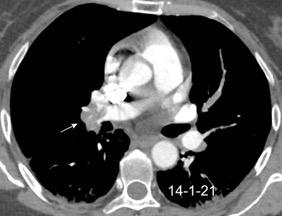

T. mixto de células germinales del testículo izquierdo

Nódulos pulmonares múltiples. (flechas verdes). Masas paratraqueales. (flechas amarillas). Dudoso ensanchamiento retrocrural (flechas negras). sigue….

T. mixto de células germinales del testículo

izquierdo Metástasis pulmonares. (flechas verdes). Ganglios paratraqueales. (flechas amarillas). Ganglios retroperitoneales (flechas negras)

Tawfik A et al. Trans-diaphragmatic Pathologies: Anatomical Background and Spread of Disease on cross-sectional Imaging. Current Problems in Diagnostic Radiology. 2021.